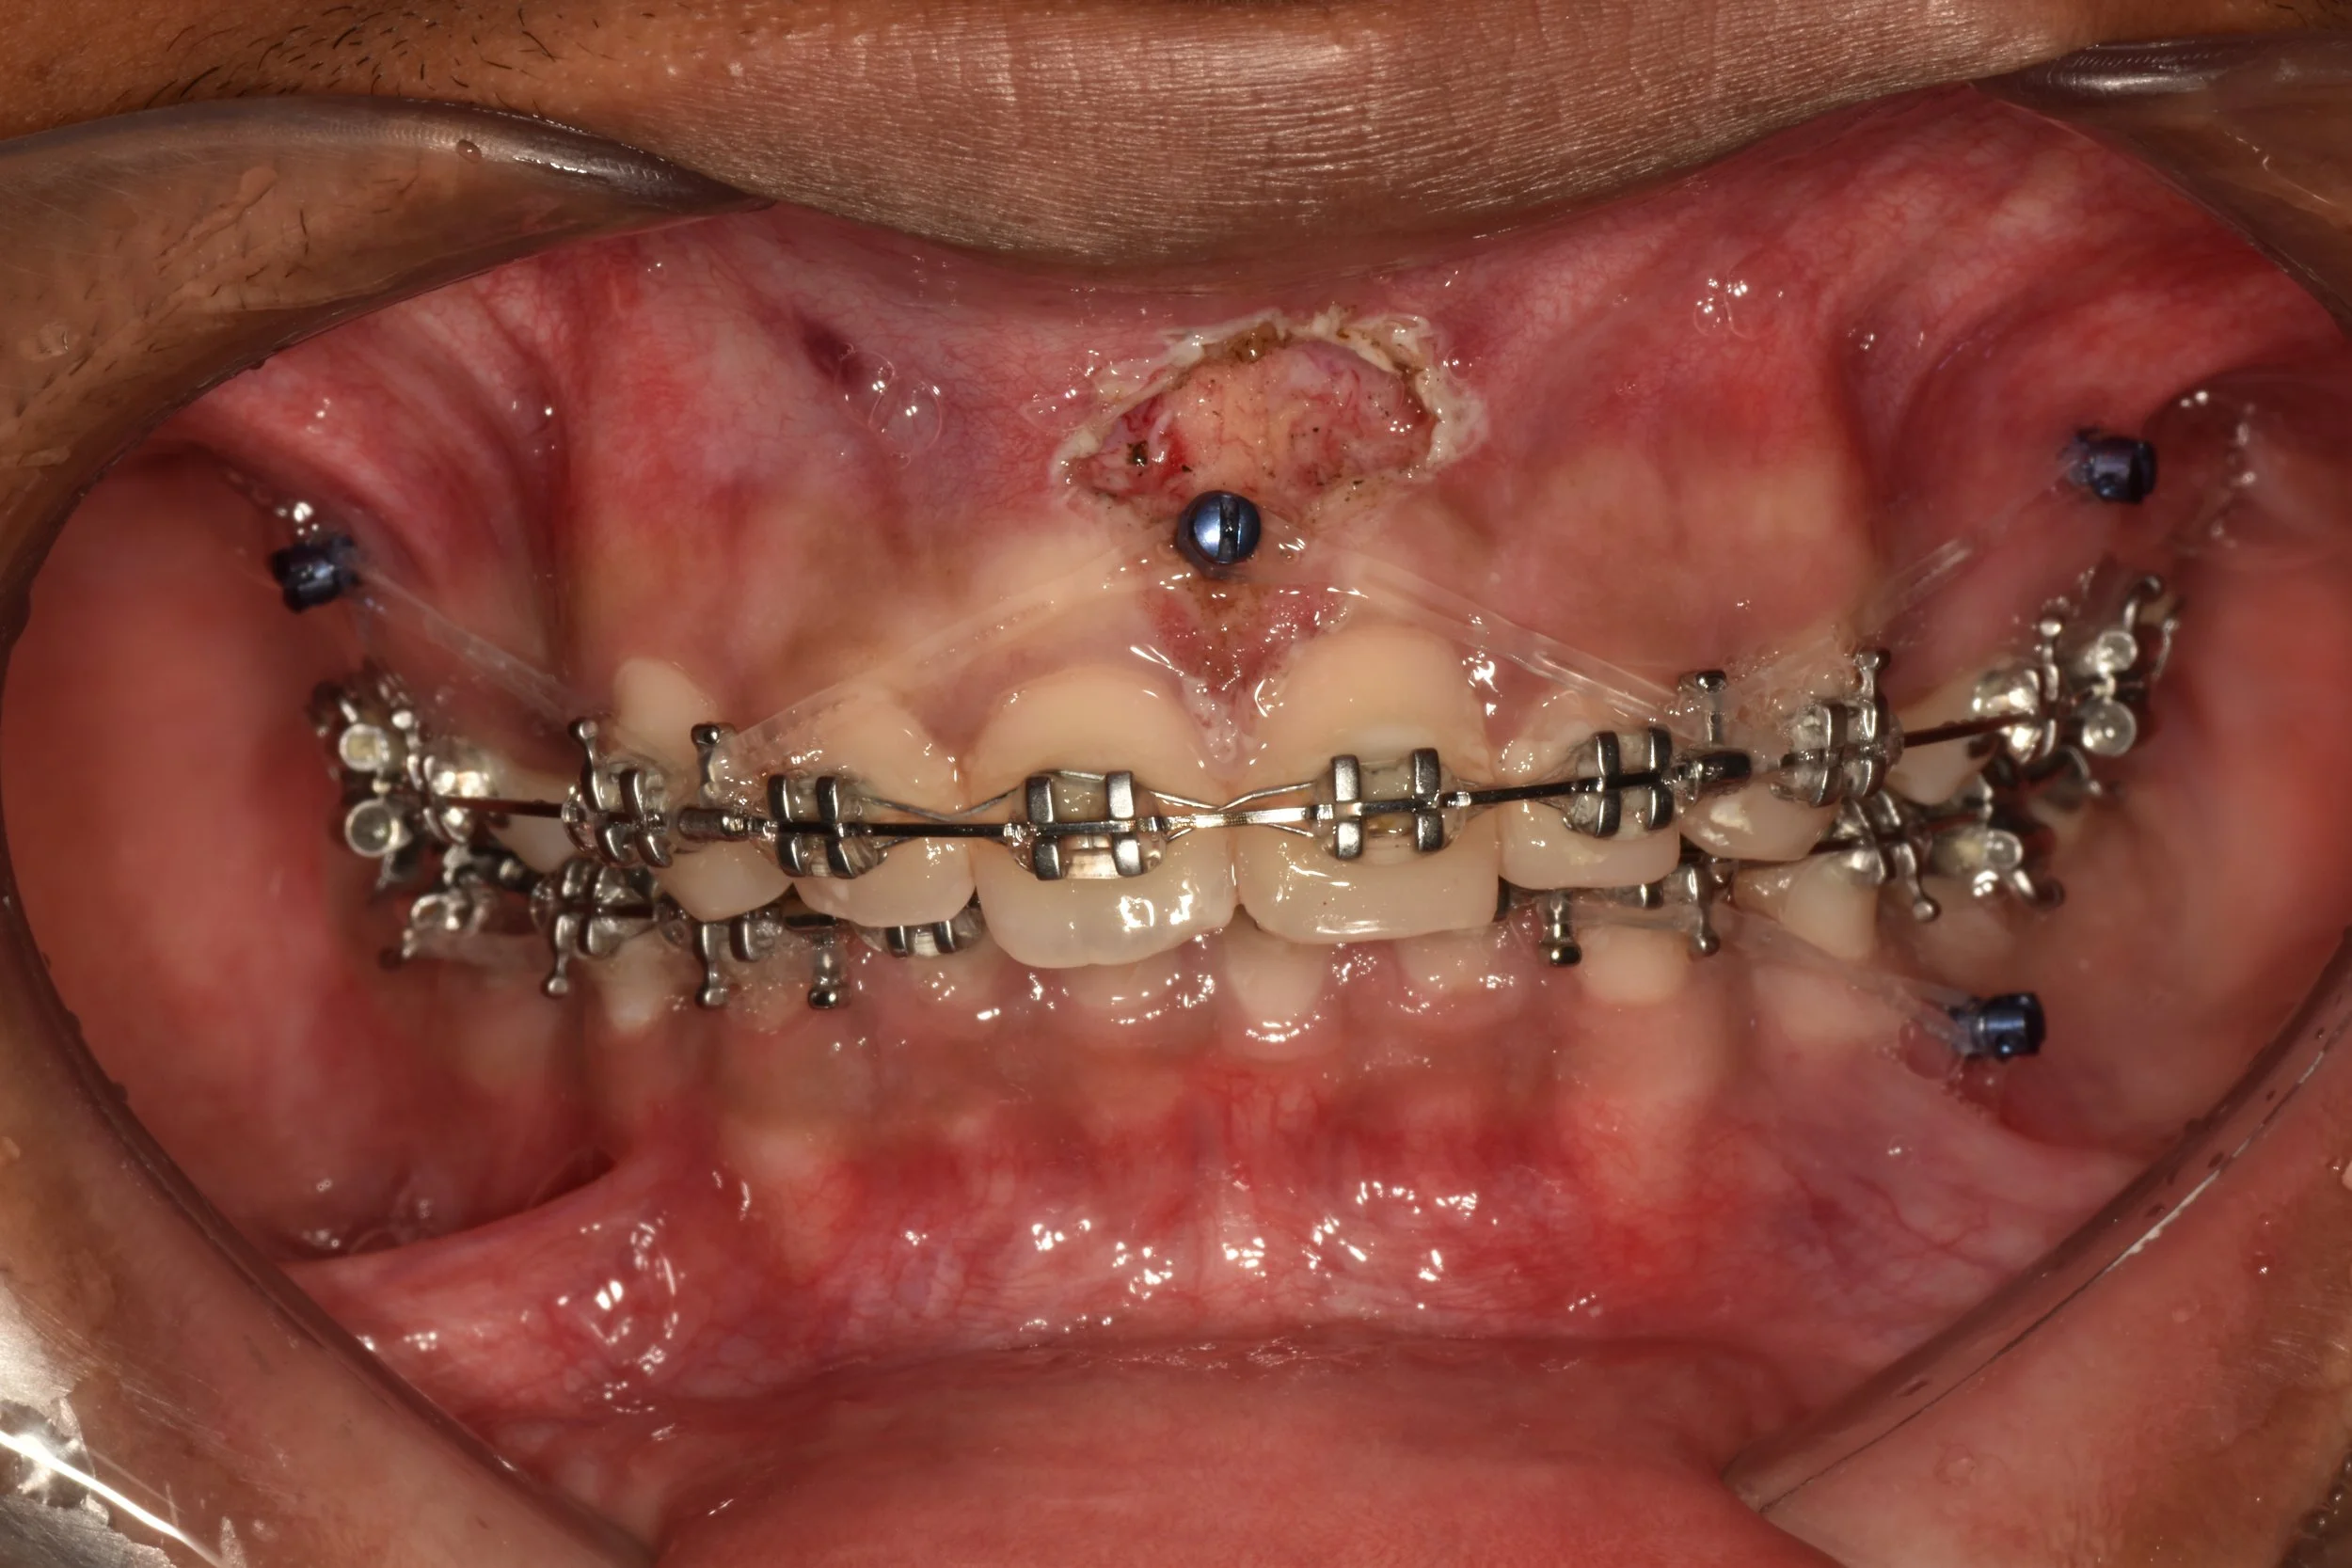

Extra-radicular implants